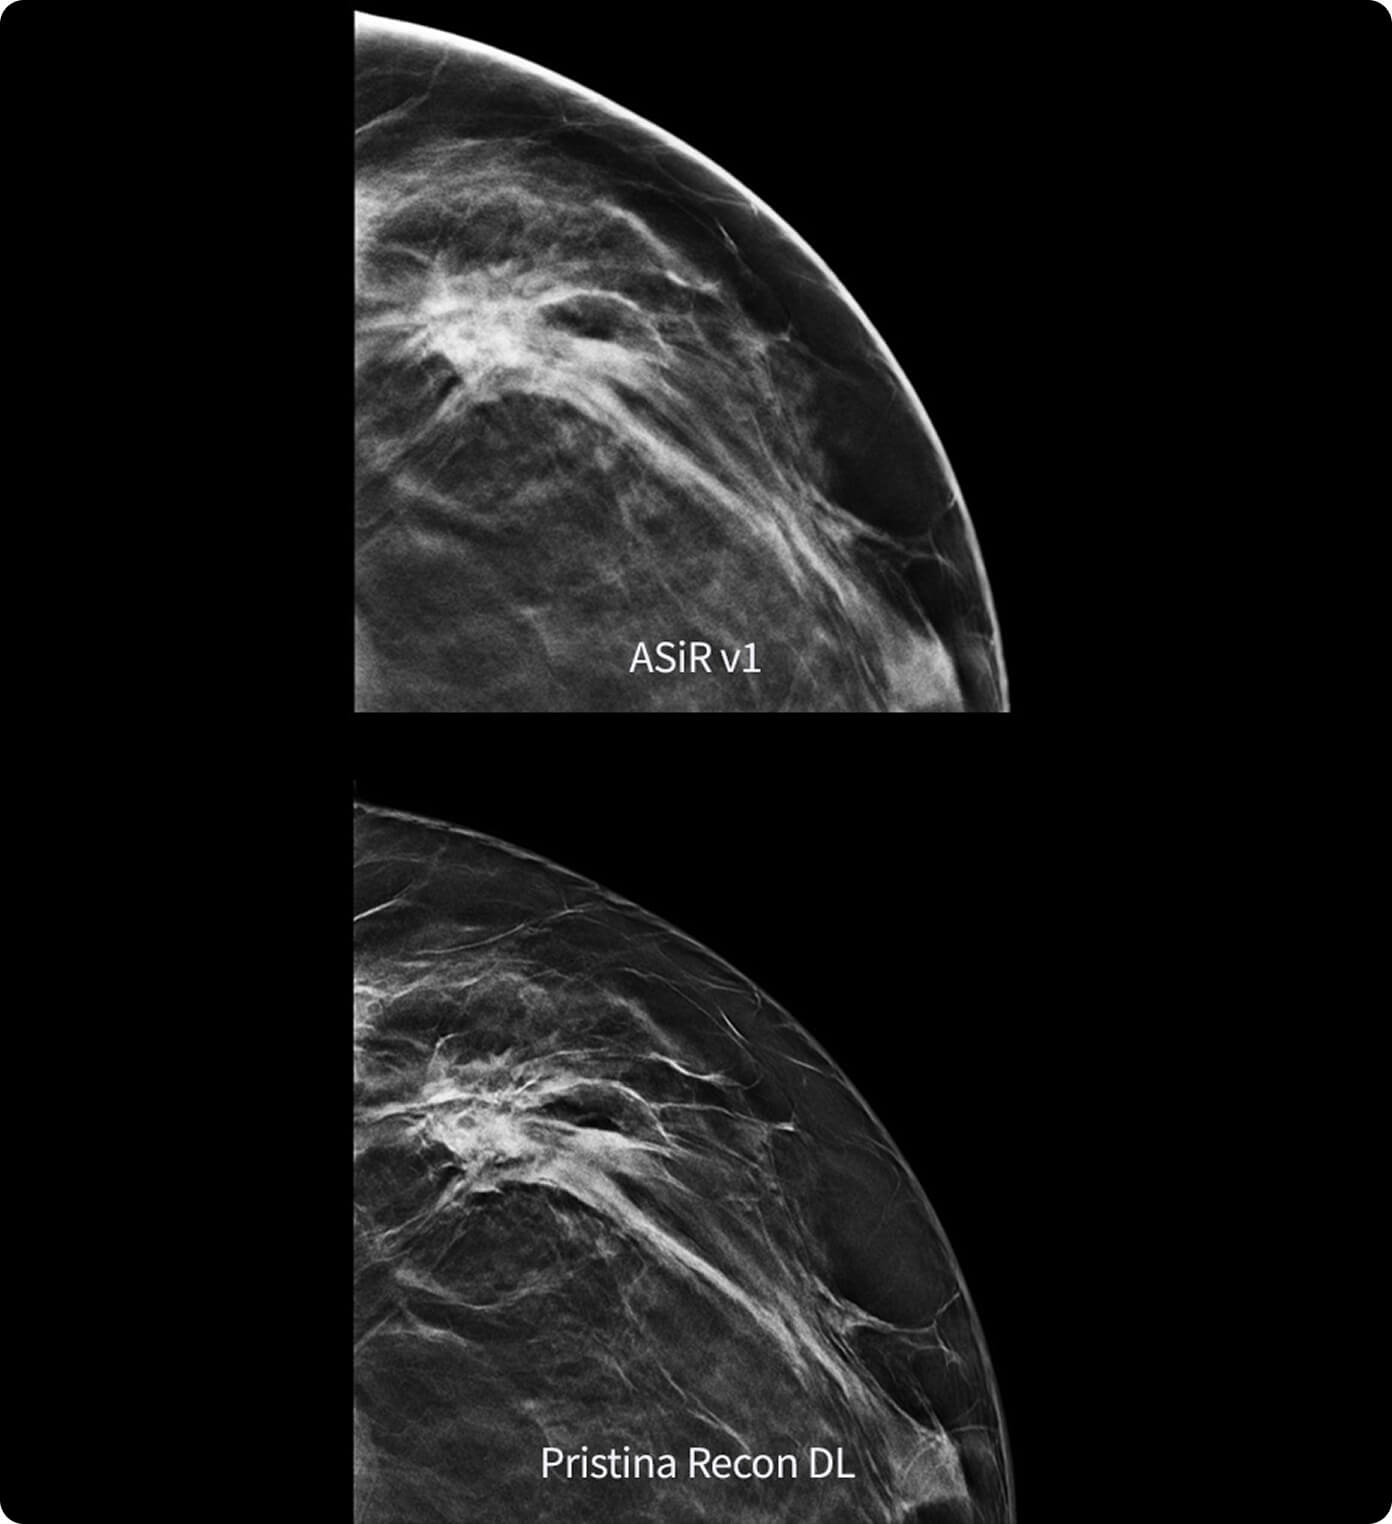

Pristina Recon DL*

The power to detect. The confidence to decide. Introducing groundbreaking technology in mammography image reconstruction, with precision you can see.

Pristina Recon DL gives you the power to detect and confidence to decide.

It pushes the limits of 3D mammography, delivering images with greater purity.

Born from GE HealthCare's pioneering AIR Recon DL in MRI, it represents a paradigm shift in image reconstruction.

Its dual deep learning technology reveals fine details minimizing artifacts and perceived noise1,2, without increasing dose.

Pristina Recon DL reconstructs with scientific precision, transforming breast images into pristine, clear volumes. It uses two deep learning models to improve image quality without changing the acquisition.

The improvement is easy to see, with radiologists surveyed consistently preferring its sharpness1,2 and lesion conspicuity1,2.

1. Preference study performed on 140 study cases with 8 MQSA-approved radiologists, trained on clinical image quality by ACR, comparing Pristina Recon DL to ASiR v1.

2. Reader performance evaluation on 19 680 reads with 8 readers using modeled clinical data comparing Pristina Recon DL and ASiR v1.